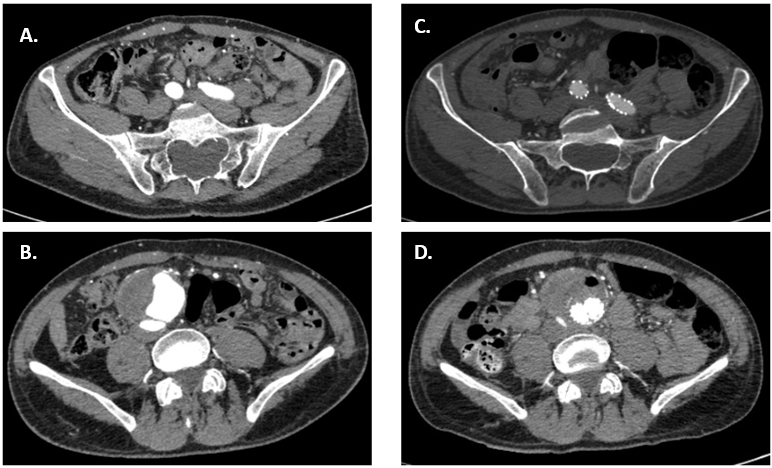

Fig. 5.Pre and Postprocedural CT of the aorta and iliac arteries. On the left (A,B), axial views of CTA at aneurysm site (B) and iliac arteries (A), preoperative. On the right (C,D), axial views of the CTA at aneurysm site (D) and iliac arteries (C), postoperative.